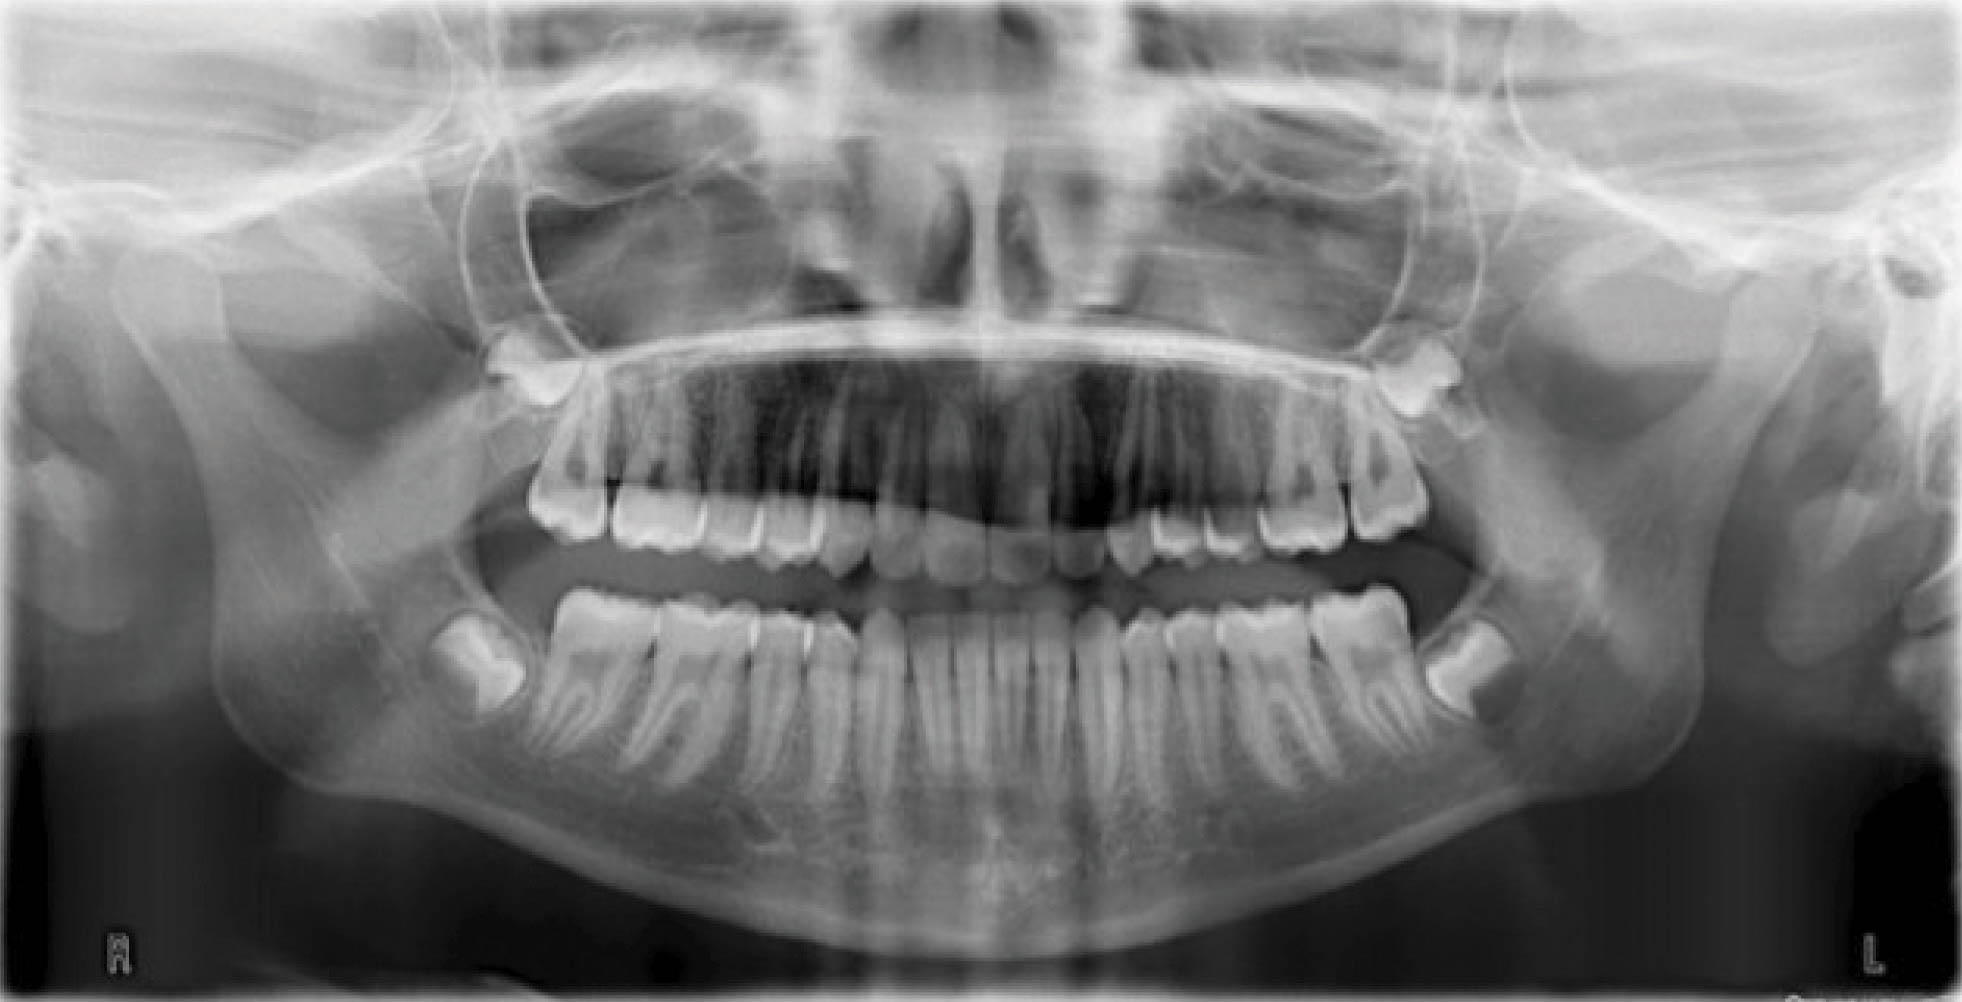

بیمار بعدی یک دختر ۱۶ ساله ClII/1 با اوربایت نرمال و اورجت زیاد است. کرادینگ مختصر دو فک دارد، قوس بالا تنگ، و پروفایل او طبیعی است (شکل 83-۶ الی 85-۶). در این بیمار از الاستیک کلاسII استفاده شده است. الگو اسکلتی طبیعی، رادیوگرافی لترال سفالومتری نشان دهنده دندانهای قدامی پروترود شده بالا با الگو طبیعی اسکلتی میباشد. رادیوگرافی OPG طبیعی است. قسمت بعُد افقی چک لیست را به این نحوه پر کردیم:

شکل 83-6